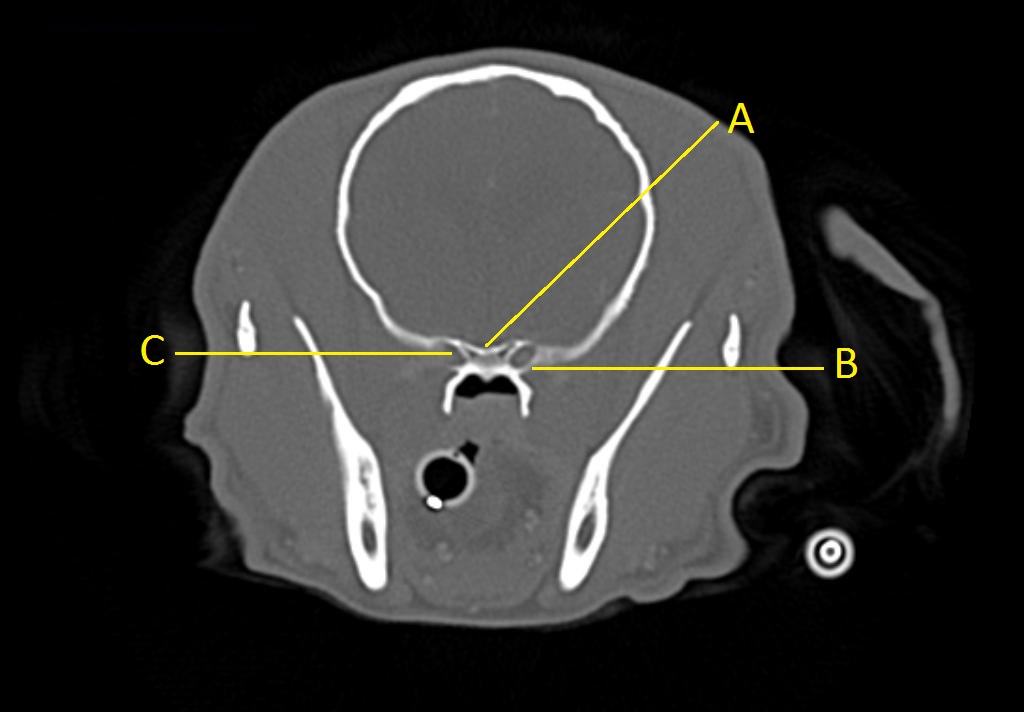

Q. Identify the structures labeled below:

A.

A. optic chiasm

B. orbital fissure

C. rostral alar foramen